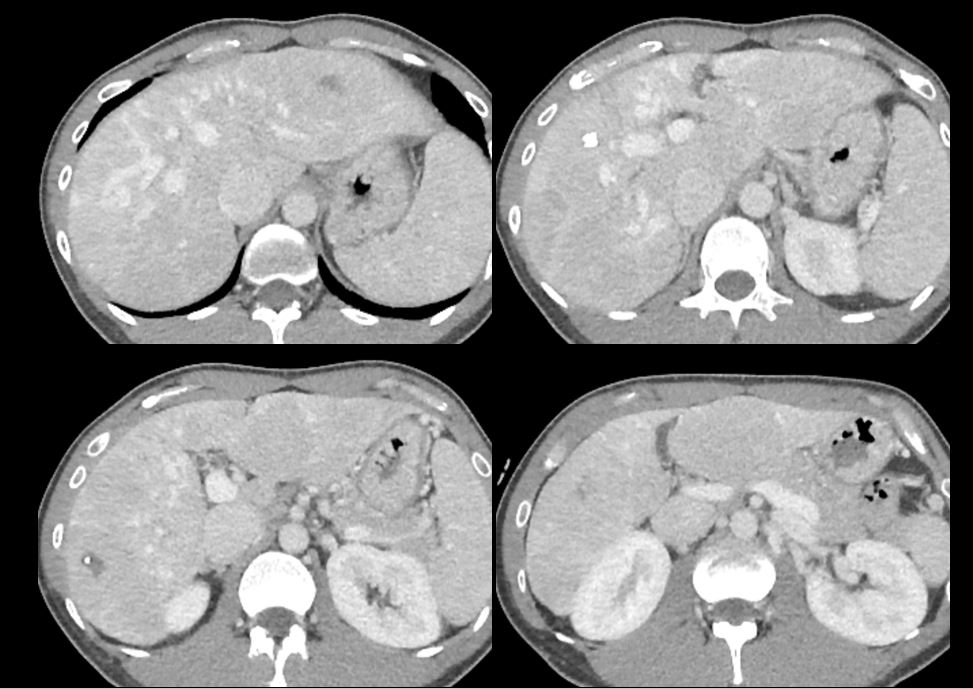

Case

No.724

F / 48

Abnormal finding on AP CT

ABDOMEN

»ï¼º¼¿ïº´¿ø ¹ÚÁö¿¬

CASE 1

2